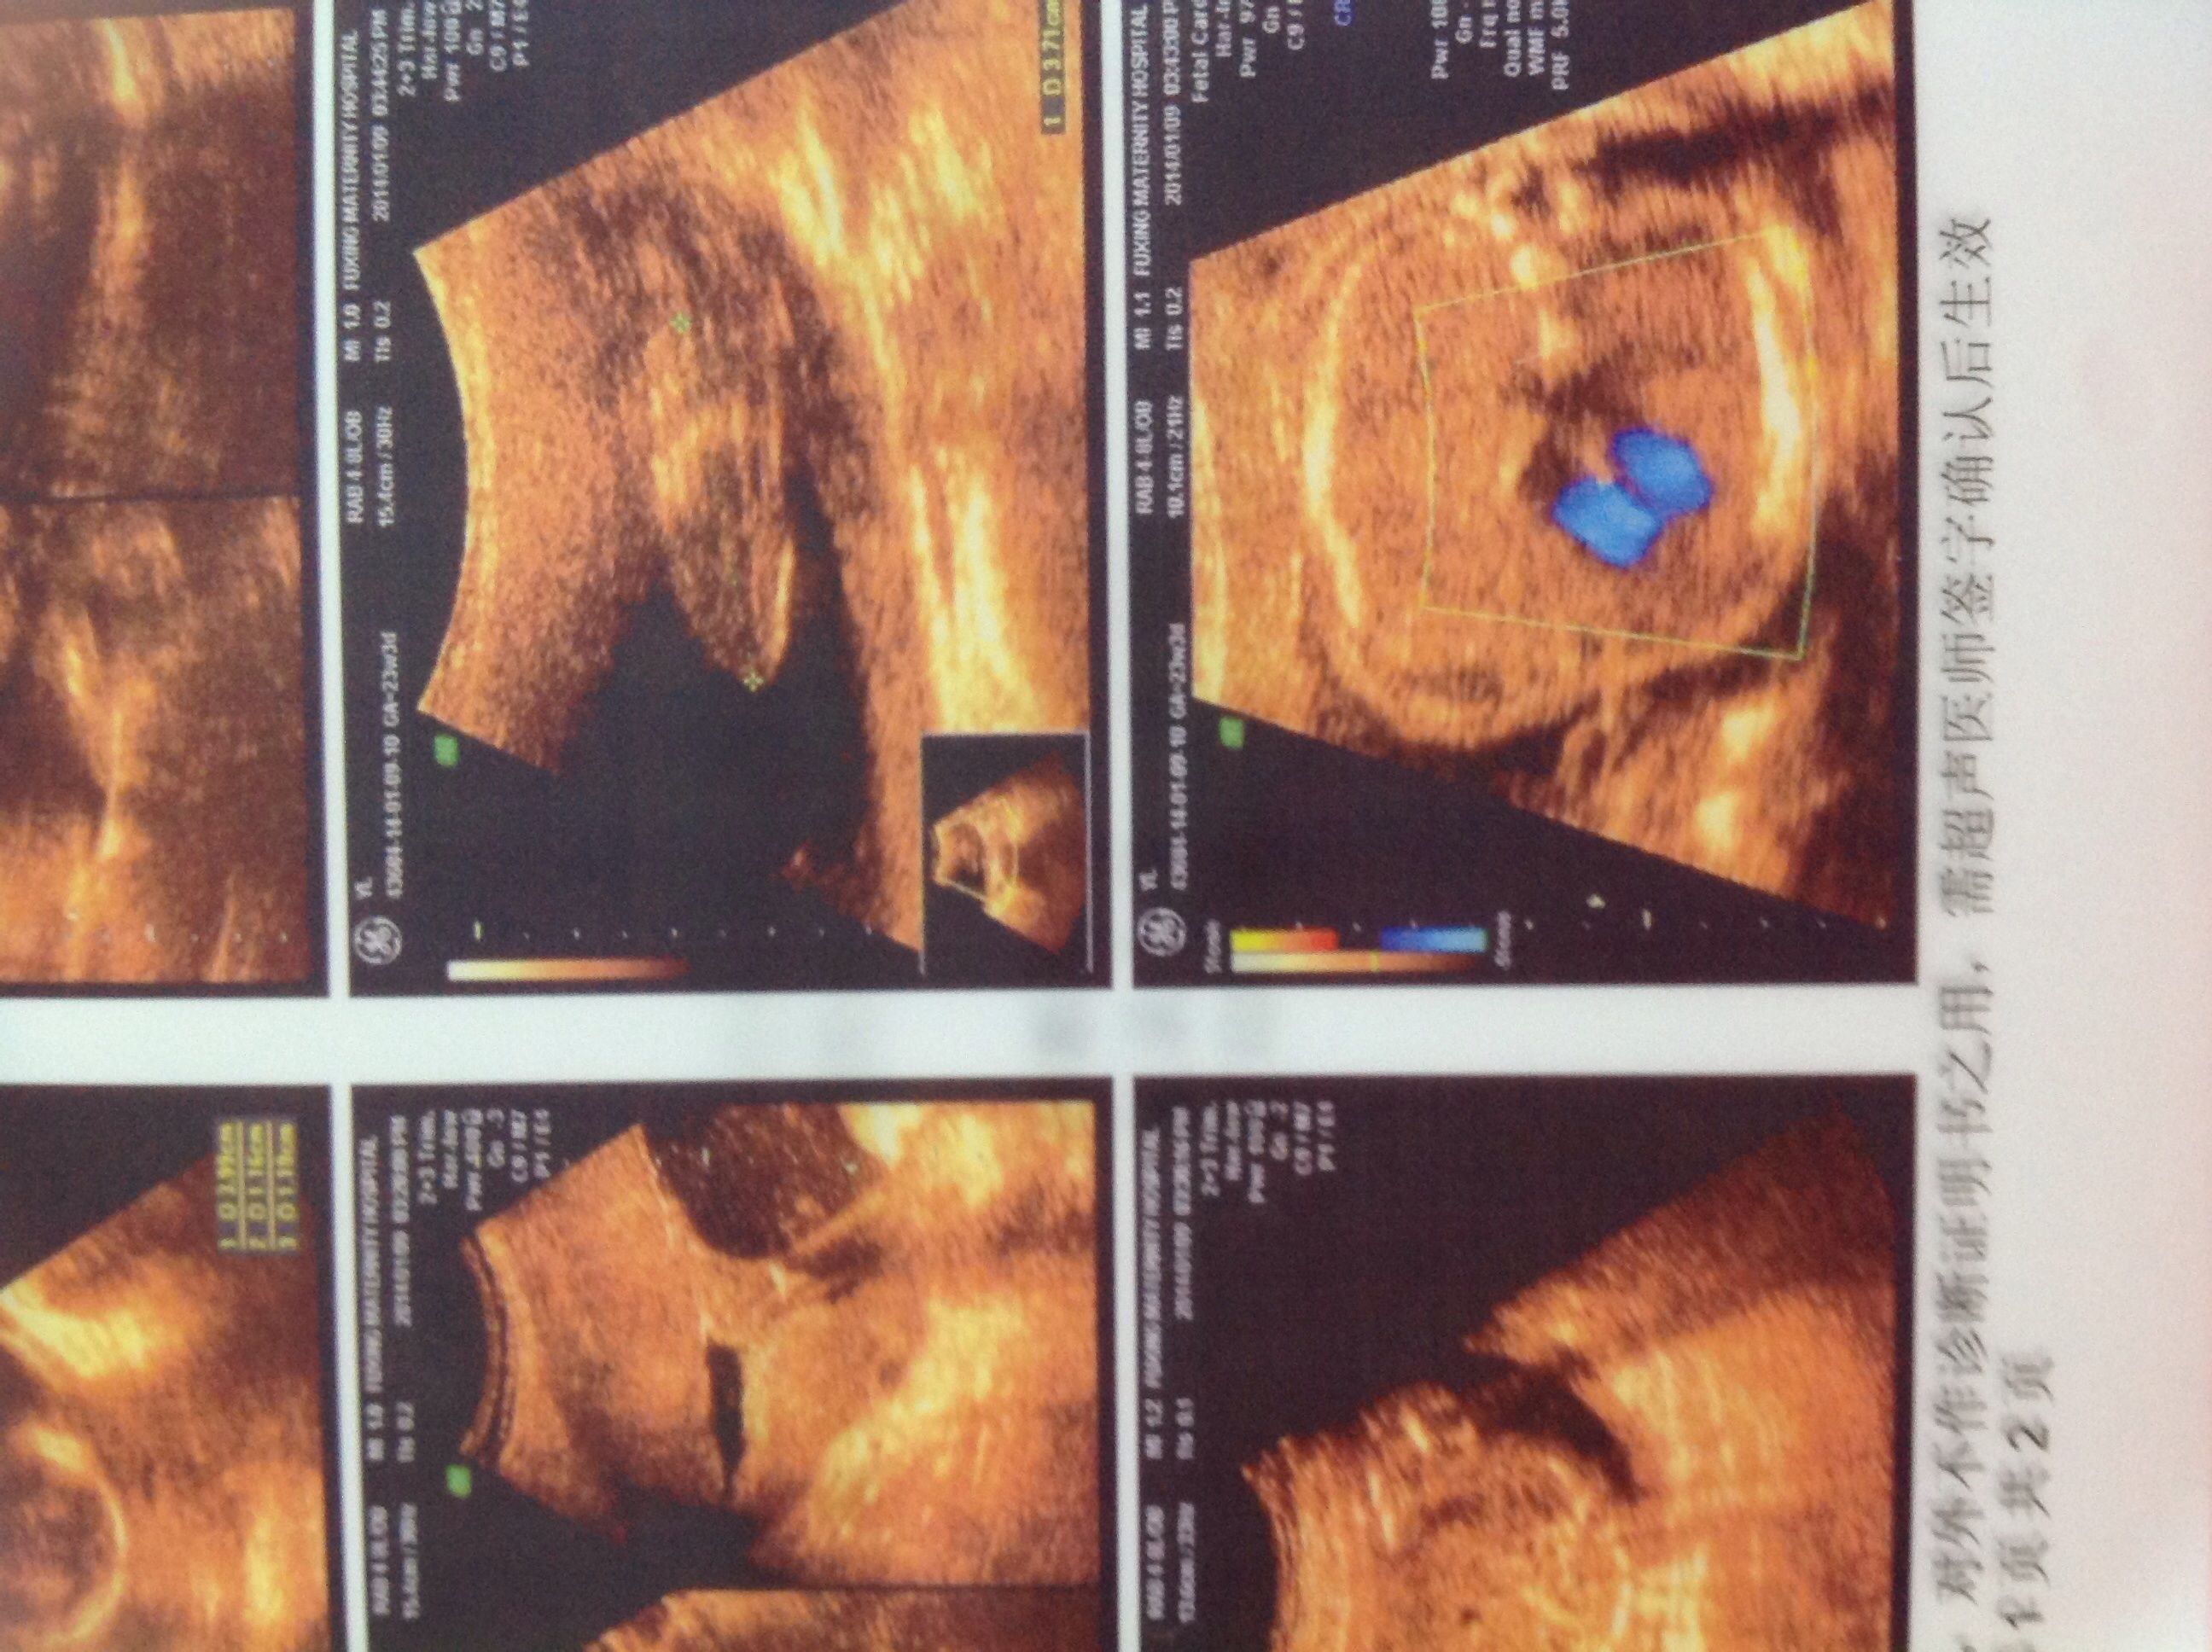

这是前两天给宝宝拍的四维彩超,现在已经22周啦,麻烦各位告诉我下是男宝宝还是女宝宝我好早做准备呢 万分感谢 点击展开 匿名用户 2014-01-16 21:11 为您推荐: 其他回答 病情分析: 根据您上述描述的情况我考虑一般看男孩还是女孩这是违法的,并且看男孩还是女孩这样也是看不出来的。 指导意见: 我考虑您就不要有这种想法了,我考虑您最好就顺其自然吧,这样没有什么需要特殊准备的。 匿名用户 2014-01-17 16:02 相关问题 在广州去哪里照四维彩超好点!?谢谢大家,麻烦知道的宝妈们告诉我一下 潞河医院做一个四维彩超多少钱啊,有知道的吗,麻烦告诉我一下 武汉哪里可以照四维彩超啊?需要花多少钱?麻烦有经验的告诉我!谢谢